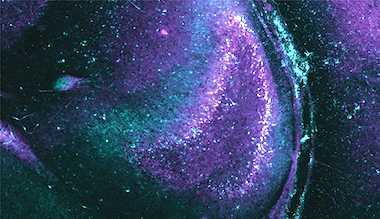

One particular finding relates to a harmful feedback loop in a region of the brain called the dentate gyrus, leading to a seizure-like event in which neurons organize their activity into wave-like patterns propagating first in one direction, and then much larger wavelike patterns that propagate at 90 degrees to the initial waves.